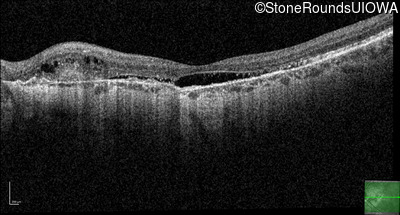

Age at visit: 56 years